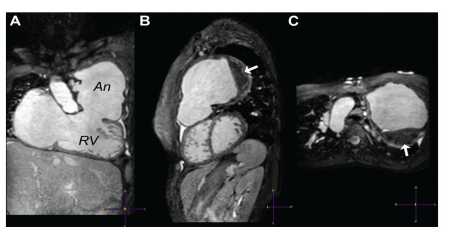

6. Resonancia magnética (RM): Es el gold estándar para la evaluación cuantitativa de tamaño y función biventricular, medidas de flujo y viabilidad miocárdica 61. Los objetivos de la RM en la TOF reparada son: 1) evaluación cuantitativa de los volúmenes del VI y VD, masa y fracción de eyección (FE); 2) cuantificación de la insuficiencia pulmonar, regurgitación tricuspídea, Ge y relación de flujo pulmonar/sistémico; 3) evaluación de anomalías regionales del movimiento de la pared; 4) imágenes de la anatomía del tracto de salida del VD, arterias pulmonares, aorta y colaterales aortopulmonar; 5)evaluación de viabilidad miocárdica, incluido tejido cicatricial en el miocardio del VD, además de los sitios de cirugía previa; 6)evaluación de derivación intracardíaca o extracardíaca residual; 7)evaluación de la válvula aórtica para regurgitación y medición de tamaño aórtico; y 8)evaluación de las arterias coronarias 62,63 (figura 10) 60.

Figura 10 RMN de gran aneurisma del flujo de salida del VD con trombo asociado en paciente con TOF. (A) Imagen Cine SSFP en un plano coronal oblicuo que muestra el flujo de entrada y salida del VD. Nótese el aneurisma de pared delgada (An). (B) Imagen sagital oblicua del aneurisma y el trombo (flecha). (C) Imágenes en el plano axial demuestran que el aneurisma llena el hemitórax superior izquierdo. La flecha en C muestra el mismo trombo que en B.